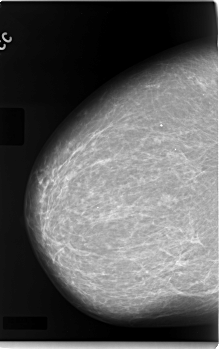

C_0083_1.RIGHT_CC

RIGHT_CC LINES 5928 PIXELS_PER_LINE 3720 BITS_PER_PIXEL 12 RESOLUTION 50 NON_OVERLAY